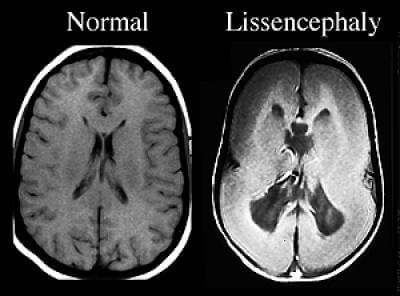

Lissencephaly

“Smooth Brain”